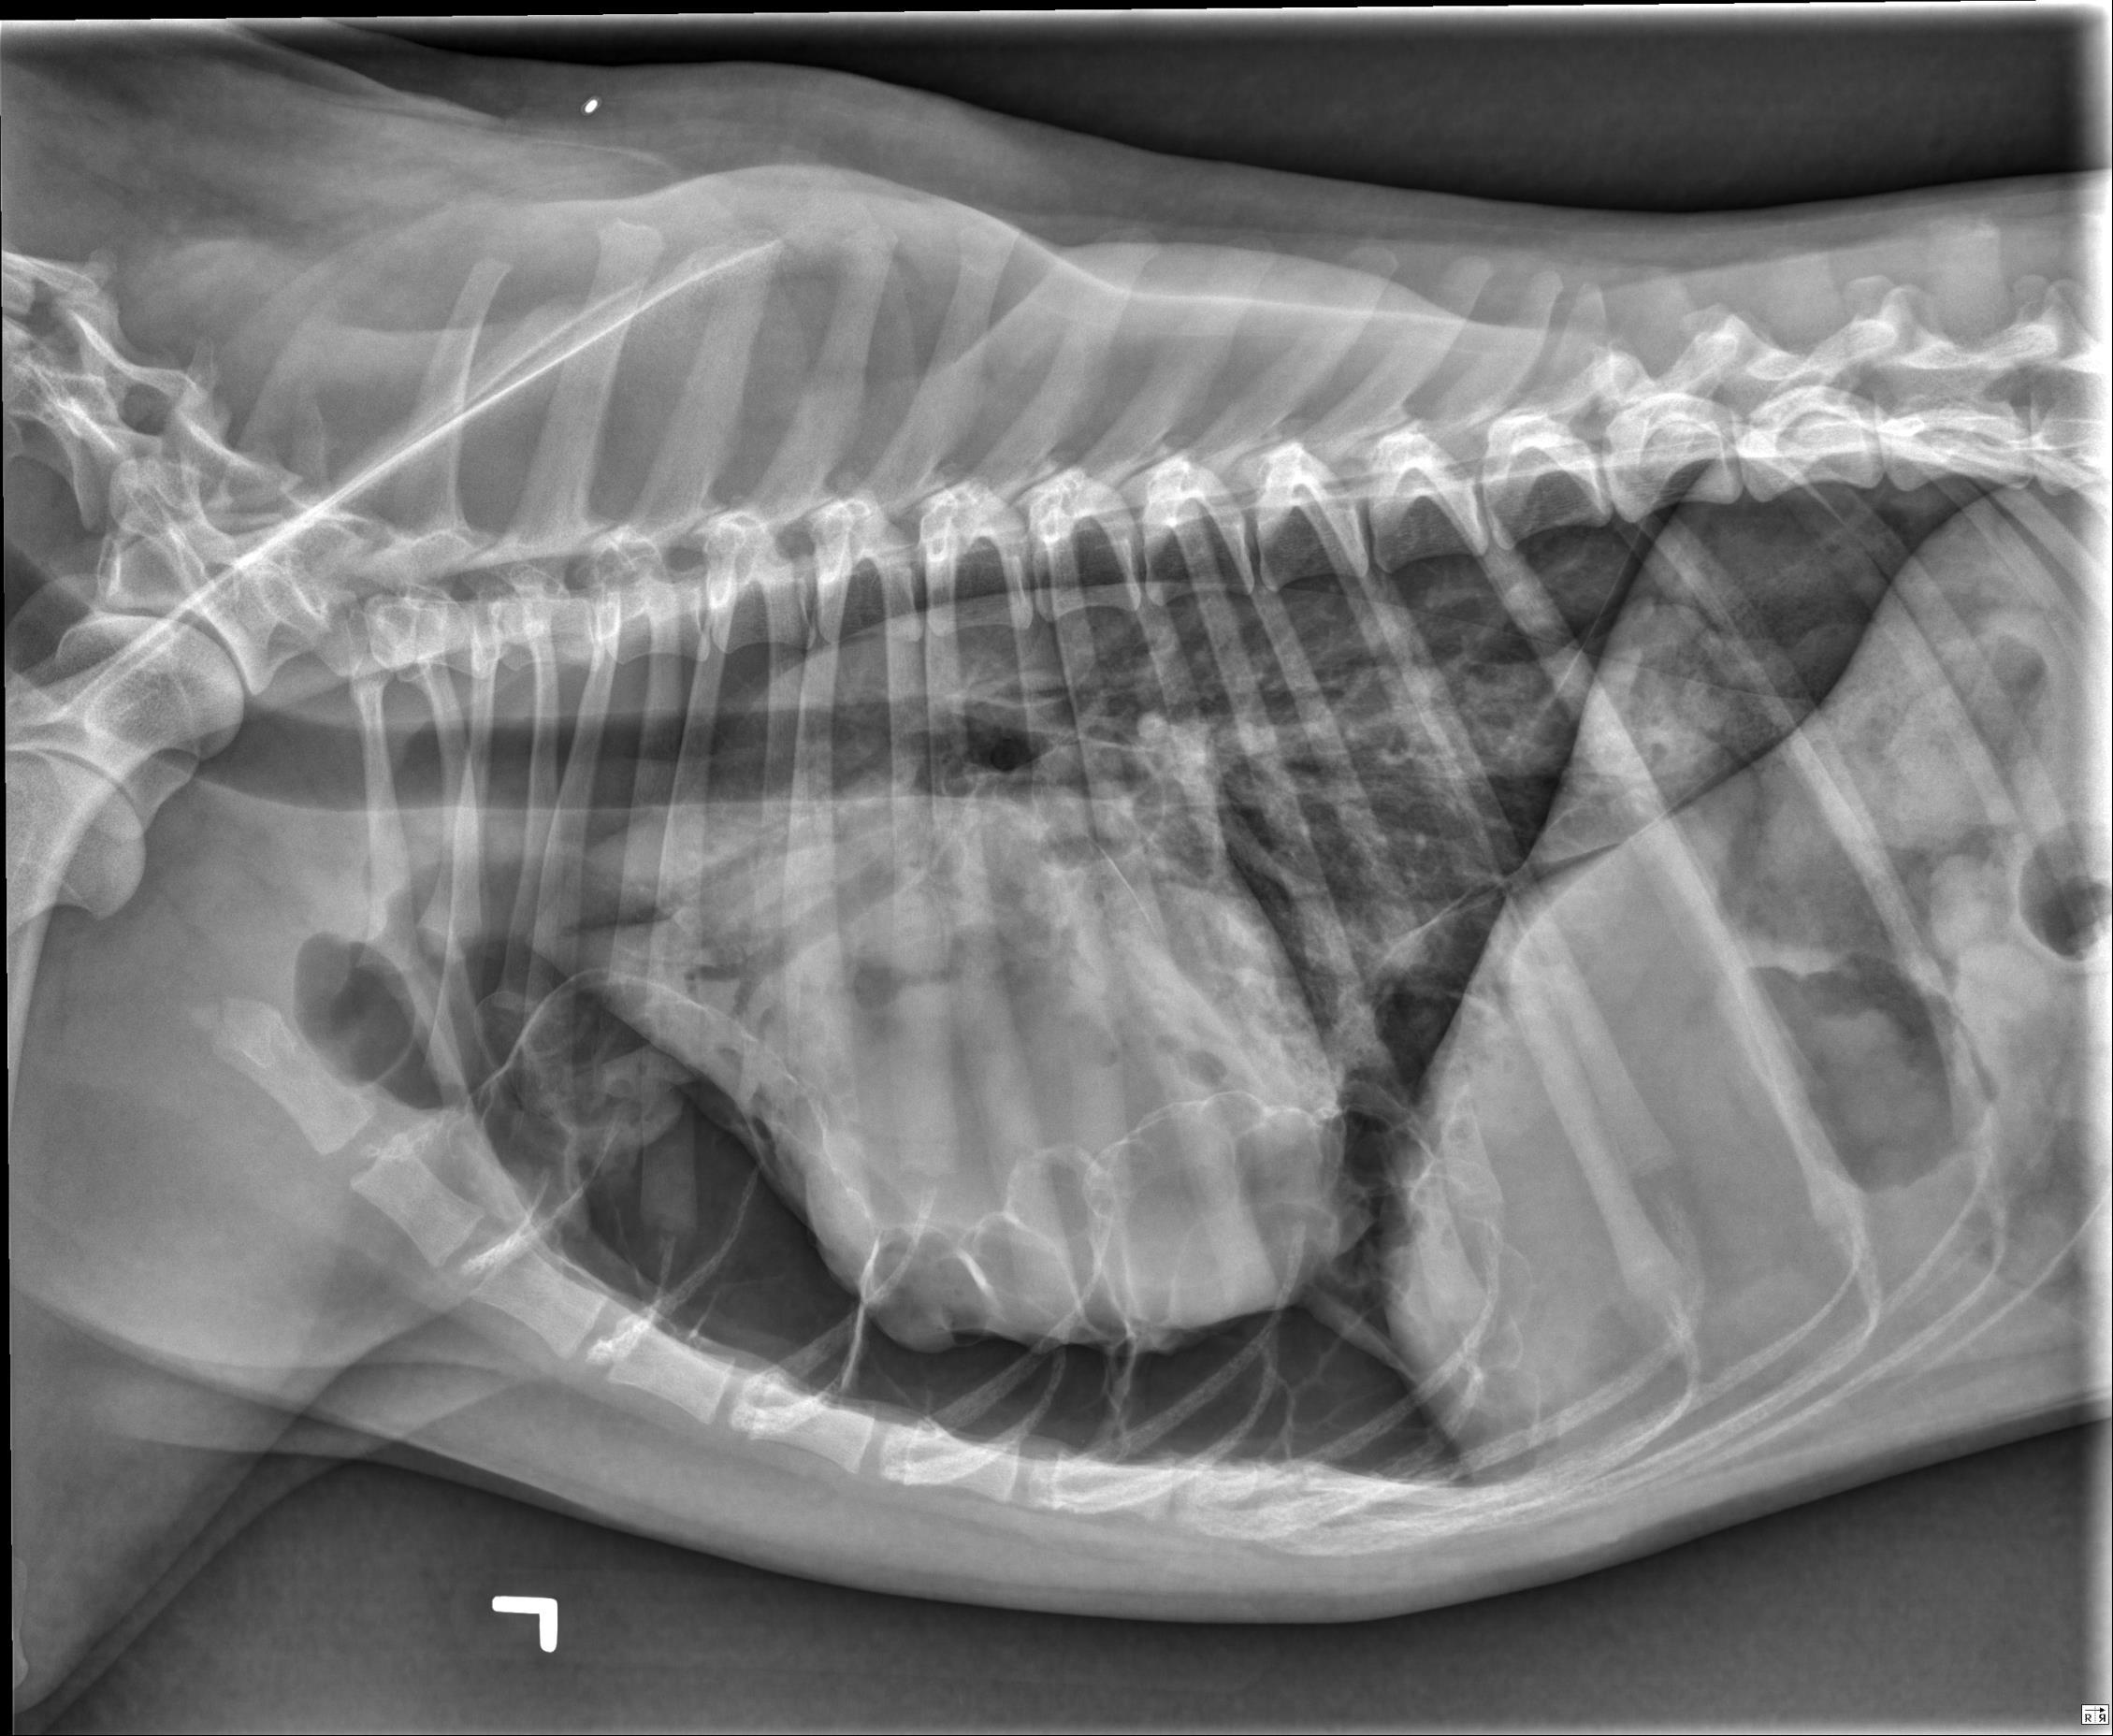

Thorax- ventrodorsal and opposite lateral radiographs are available for review.

There is a large volume of gas in the pleural space, bilaterally, with retraction of the pulmonary margins from the body wall. A smaller volume of fluid is also present. In the caudal subsegment of the left cranial lung lobe, there are two well-defined, gas filled structures with a thin, soft tissue opaque rim. The largest measures 2.7cm in diameter, and the smaller, located just cranial to the first measures 0.9cm in diameter. There is an alveolar pulmonary pattern in the ventral aspect of the right cranial lung lobe with an air bronchogram, most prominent on the left lateral projection. Throughout the remainder of the pulmonary parenchyma, there is a mild to moderate, diffuse, unstructured interstitial pulmonary pattern. Dorsal to the second and third sternebrae, there is an ovoid soft tissue structure consistent with an enlarged sternal lymph node (up to 1.6cm in thickness). The stomach contains a moderate volume of heterogenous soft tissue opaque material and gas. The musculoskeletal structures included in collimation are normal.

At least two pulmonary bullae. There is no reported history of trauma, and with the presence of at least two other pulmonary bullae, spontaneous pneumothorax secondary to ruptured bulla is possible.

Alveolar pulmonary pattern in the right cranial lung lobe may represent a focal region of more severe atelectasis (secondary to pneumothorax), however, given the history, underlying pulmonary pathology such as resolving pneumonia is also considered. The pulmonary pattern in the remainder of the lung lobes is consistent with atelectasis.

Mild to moderate sternal lymphadenopathy, likely reactive.

Gastric ingesta may be digestible or indigestible. Evidence of obstruction is not currently identified.